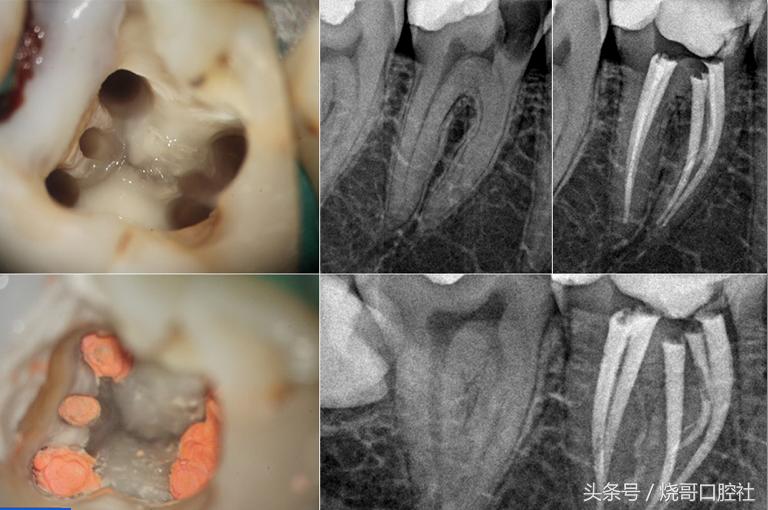

蛀牙过深牙本质被破坏,牙齿变黑而且还会剧痛,说明牙髓已经死去,牙体需要保护就得杀死牙神经,再用生理盐水冲洗,封药消炎几次,注意换药期间将拔髓针拔一下,检验是否有残髓,才可以做氢氧化钙和氧化梓双层垫底,再继续填充纳米树脂。